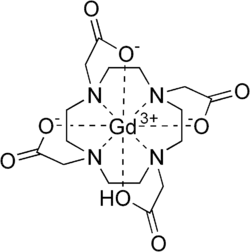

Gadoteric acid, sold under the brand name Dotarem among others, is a macrocycle-structured gadolinium-based MRI contrast agent (GBCA). It consists of the organic acid DOTA as a chelating agent, and gadolinium (Gd3+), and is used in form of the meglumine salt (gadoterate meglumine).[4][5] The paramagnetic property of gadoteric acid reduces the T1 relaxation time (and to some extent the T2 and T2* relaxation times) in MRI, which is the source of its clinical utility. Because it has magnetic properties, gadoteric acid develops a magnetic moment when put under a magnetic field, which increases the signal intensity (brightness) of tissues during MRI imaging.[7]